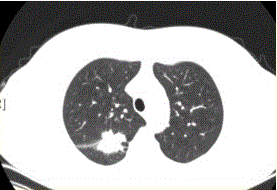

问题 患者女,54岁,无症状,常规体检透视时发现右上肺阴影。既往无结核病史。体格检查阴性。CT结果如下图。 最易出现分叶状边缘的肺癌类型是

选项 A.鳞癌 B.腺癌 C.未分化癌 D.肺泡癌 E.转移性肿瘤 F.肺类癌

答案 B